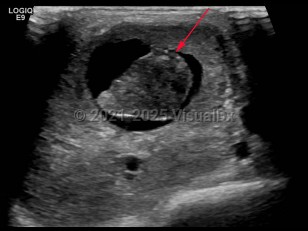

Imaging Studies image of Parotid gland carcinoma - imageId=6841392. Click to open in gallery.  caption: 'Grayscale ultrasound image of the right parotid gland demonstrating a complex partially cystic mass within the parotid gland.'

Grayscale ultrasound image of the right parotid gland demonstrating a complex partially cystic mass within the parotid gland.